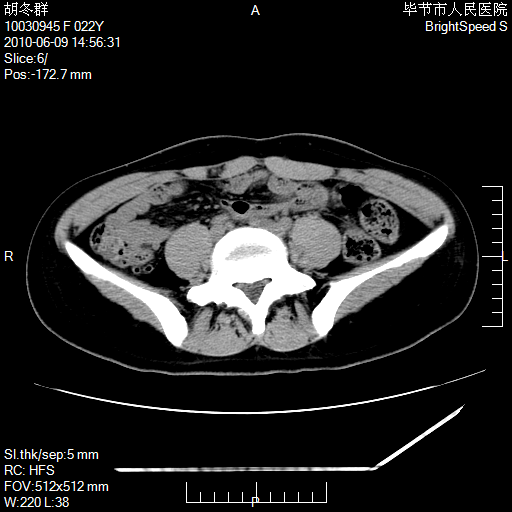

患者23岁,发现腹部包块3月。

盆腔内囊性占位;穿刺或者直接手术拿掉即可,不必紧张。

盆腔内囊性占位性病变;考虑左侧卵巢囊腺瘤。

有分隔、壁薄,支持考虑左侧卵巢囊腺瘤。

左侧卵巢浆液性囊腺瘤。

有分隔、壁薄,支持考虑左侧卵巢囊腺瘤。排尿后,膀胱缩小,由于重力作用,肿块下移就到了膀胱位置,很好理解。